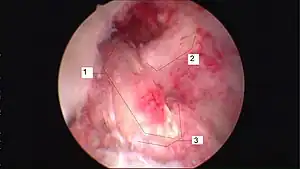

| Arthroscopic anterior cruciate ligament (ACL) reconstruction (right knee). The tendon of the semitendinosus muscle was prelevated, folded and used as an autograft (1). It appears through the remnant of the injured original ACL (3). The autograft then courses upwardly and backwardly in front of the posterior cruciate ligament (2). | |